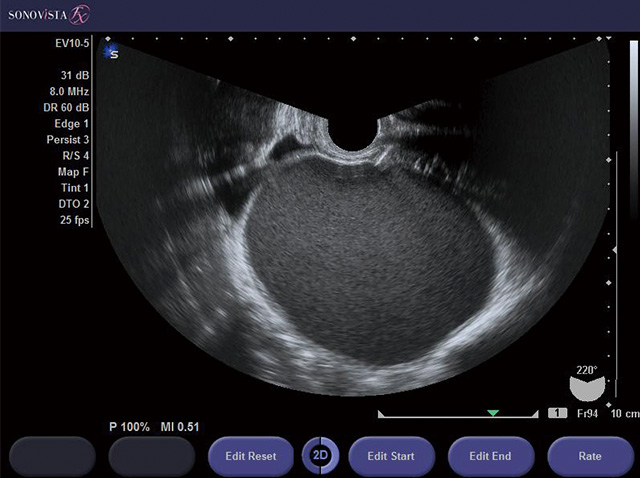

子宮筋腫、卵巣腫瘍、子宮内膜肥厚(子宮体がんの疑い)など 腟超音波(エコー)検査 画像で子宮や卵巣の状態を確認します。お腹の上から器具(プローブ)をあてる方法と腟の中にプローブを挿入する方法があります 女性におすすめしたい健康診断をご案内しています。久屋大通駅、栄駅すぐ1つ目は影の形。 子宮筋腫は滑らかな円形をしています。 「淡い影は細長く、筋腫にはありえない形をしています」(森山さん) 2つ目は影の濃さ。 「MRIの画像では、筋腫は真っ黒に、がんはそれより淡い色に写るようになっています。 仮にがんが見を比較し,下腹usの精度が低いと考えられる要因や,病変のとらえ方の相違などを,子宮筋腫 の観察を用い検討することで明らかにする. 対象と方法:対象は14年4月1日から15年3月31日までに当センターの二日ドックを受診し, オプション検査として経膣usを実施した2 6名.経膣usと下腹usの

子宮筋腫とは? まずは初歩的な、子宮筋腫について軽く紹介します。 35歳以上で~30%、40歳以上で40~50%の方が子宮筋腫もち。 この数字を見てもわかるように、子宮筋腫は女性特有の病気で、4人に1人が抱えているありふれた病気。また、エコー写真の見方を説明しています。超音波検査 子宮のなかに胎嚢があるどうか 子宮や卵巣異常のチェック 胎児の心拍を確認 胎児の大きさ 胎児のトラブル超音波検査は主に2つの検査方 お腹の超音波エコーでたまたま子宮筋腫が見つかりました子宮卵巣エコー 超音波の原理を使った検査法で、体内に超音波を送り、跳ね返ってくる反射波(エコー)をとらえることによって、体内の情報を画像化する検査です。 痛みはほとんどなく、超音波機器の発達で、安全で簡単に子宮や卵巣を詳しく検査できるようになりました。 放射線を使わない

医師監修 経膣超音波 エコー 検査 はぐふる